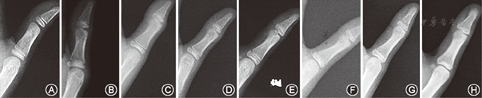

在站立位全脊柱正位片上测量主弯Cobb角,根据每次患者随访时的身高算身高生长速率(HV)=[身高n-身高(n-1)]/[时间间隔n-(n-1)],患者每次随访时HV值的最大值定义为HV峰值(PHV)[10]。由两位脊柱外科医师(脊柱外科主治医师和住院医师各1名)分别根据患者每次随访时拍摄的左手掌正位片计算DSA评分[11]和RUS评分[12],同时应用Hung等[9]提出的TOCI评分系统计算TOCI评分,同一手片两位医师评分结果一致时方才采用,否则重新进行评分。记录每张左手掌正位片进行3种评分各自所花费的时间。TOCI评分系统定义见图1,图2。